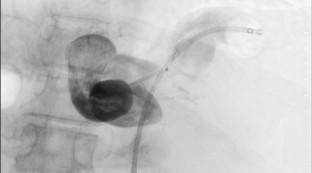

Sofosbuvir/velpatasvir (SOF/VEL) is expected to be highly effective, even in patients with decompensated liver cirrhosis. However, portal hypertension can be problematic after achieving a sustained viral response (SVR), especially in patients with hepatic encephalopathy (HE) associated with large portal-systemic shunt. Although balloon-occluded retrograde transvenous obliteration (BRTO) is a useful option, whether BRTO or SOF/VEL therapy should be initially performed in patients with a poor liver function reserve is controversial. We herein report a case of refractory HE caused by decompensated liver cirrhosis due to hepatitis C virus (HCV) classified as Child–Pugh class C that was treated by BRTO after SVR with SOF/VEL. A 64-year-old woman with HCV-associated decompensated cirrhosis developed refractory HE. Dynamic contrast-enhanced computed tomography (CT) revealed large portal-systemic shunt. We treated the patient with 12 weeks of SOF/VEL, and she achieved SVR. Although the serum albumin level, edema, and ascites were improved, intractable HE remained. Her general condition had been improved after SVR, so HE was suspected to have been caused by portal-systemic shunting. We, therefore, treated the patient by BRTO. On dynamic contrast-enhanced CT, partial obstruction of the shunt vessel was confirmed after BRTO. Thereafter, her serum ammonia level rapidly improved, and HE did not recur. Interventional radiology such as BRTO following SOF/VEL therapy may be a useful option even in patients with decompensated HCV-associated cirrhosis accompanied by portal-systemic shunt.

Fig. 3